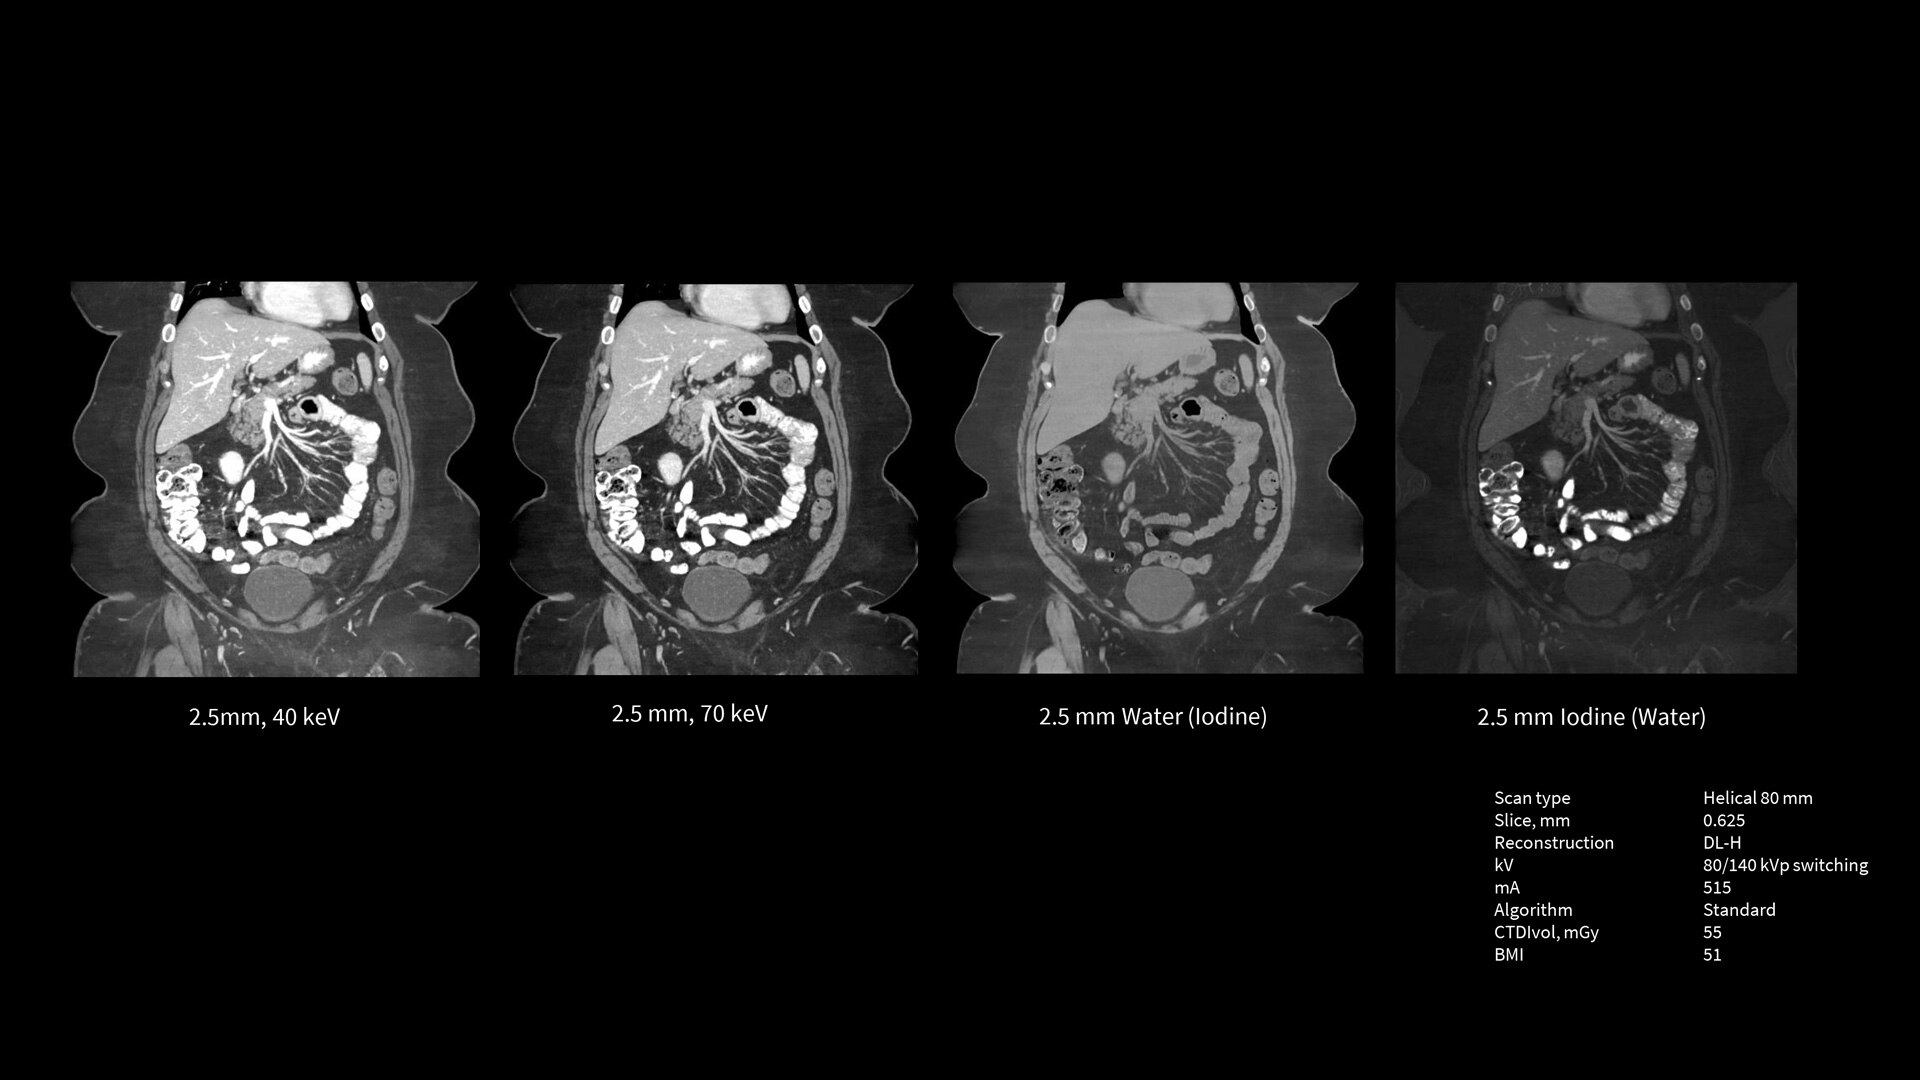

Smart Subscription for CT

Smart Subscription is the industry's first subscription-based service for CT applications. Smart Subscription includes a broad range of application packages across different imaging service lines, including cardiology, neurology, oncology and radiation treatment planning. You can pick different packages and plans to begin with, and choose more packages and upgrade your plans when you want to expand your CT capabilities.